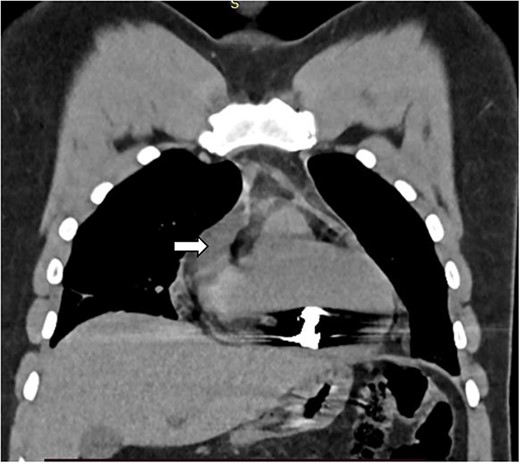

The complete blood count showed white cell count of 4300 cells, hemoglobin of 18.7 g/dl, and platelet of 285 000. Serum electrolyte, albumin and liver function tests were within normal range and creatinine was 1.19 mg/dl. Chest X ray showed bullet left of the sternum within the inferior aspect of the cardiac silhouette. Contrast CT scan detected minimal bilateral pleural collection with right basal segment atelectasis with 2.3 × 1.1 cm metallic density foreign body in the mediastinum located over the inferior border of ventricular wall (Figs 1–3). Troponin was 432.4 ng/ml. Electrocardiography showed V2 lead ST segment elevation. All the other leads were normal. The patient had three echocardiographs done, and only one showed the presence of foreign body within the myocardium of the left ventricle. Otherwise, no wall motion abnormality, or any sign of heart failure was detected.

Coronal CT image showing foreign body with in the myocardium of the right ventricle (white arrow).